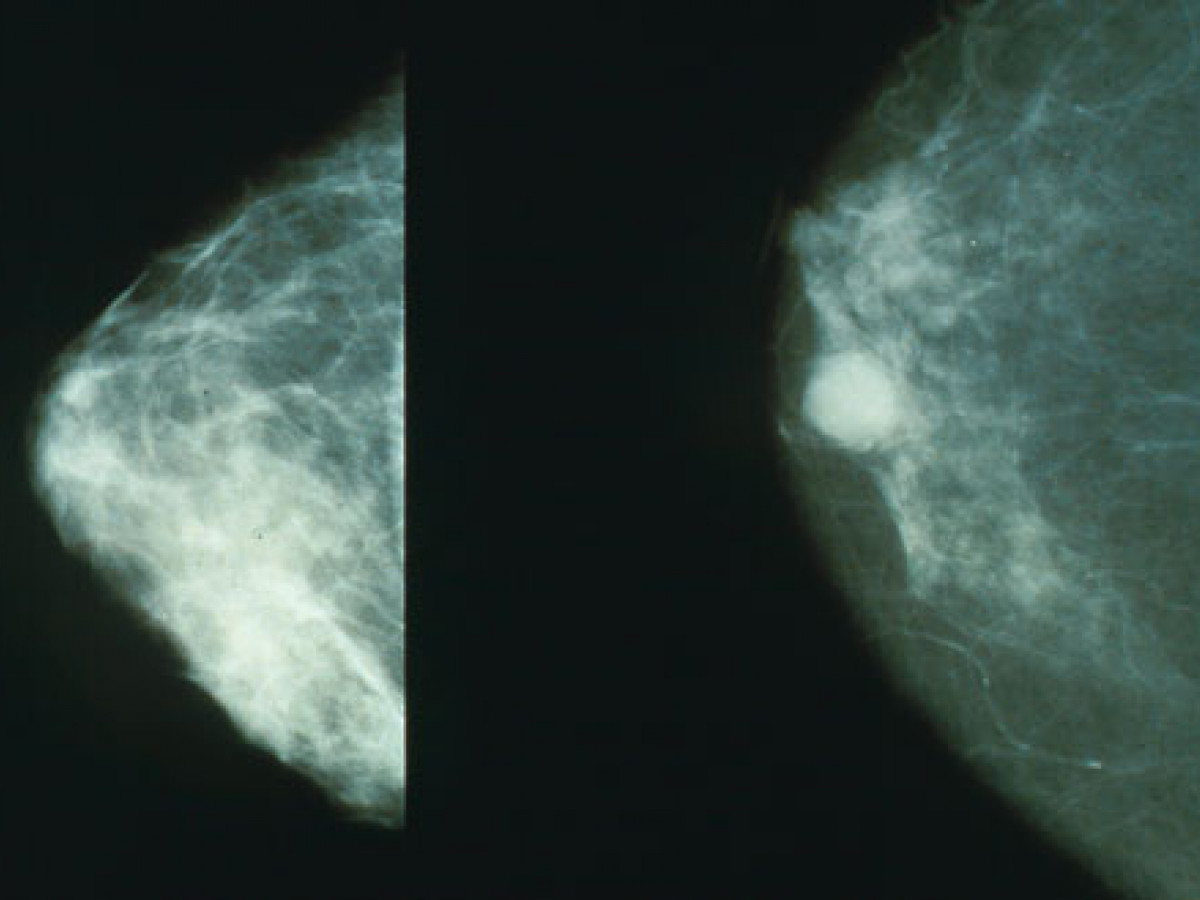

Sometimes cancers form lumps that can be detected on the outside of the body, which can make things a bit easier. Breast cancer and testicular cancer are both examples of this. Melanoma forms dark moles on the skin surface.